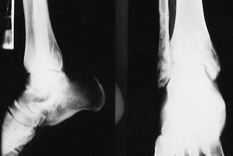

Caso clínico número 1 (Figs. 1A, 1B y 2)

Fig. 1, A y B.--Radiografía simple, anteroposterior y lateral, de ambos tobillos previa a la intervención. En el tobillo derecho se aprecian signos artrósicos avanzados. Caso clínico núm. 1.

Fig. 1, A and B.--Plain radiographs, anteroposterior and lateral, of both ankles before surgery. The right ankle shows signs of advanced arthrosis. Clinical case 1.

La radiografía simple muestra importantes cambios degenerativos en la articulación tibio-peroneo-astragalina (pinzamiento de la interlínea articular, osteofitos, etc.).

En la actualidad, presenta molestias importantes en tobillo derecho, observándose en la radiografía simple colapso astragalino, reabsorción ósea periprotésica y gran deformidad articular. Se propone para artrodesis de tobillo por movilización de la prótesis.